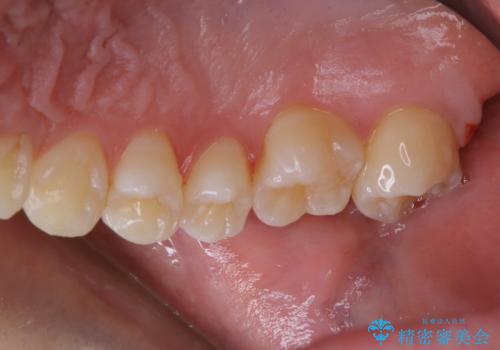

3カ月に1度のPMTCでオーラルケア

- 3カ月ごとに定期的にメンテナンスにいらしている方です。PMTC30分コースを行いました。

PMTC(保険外治療)は、毎日の歯磨きで落としきれない汚れや、タバコのヤニなどの着色も除去します。目には見えない歯と歯の間・歯肉の境目などに残っているプラーク(歯垢)もしっかり取り除きます。